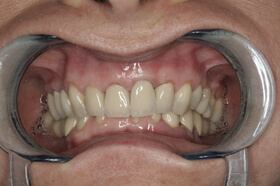

A kezelés végén a fogszabályozó készülék eltávolítása előtt